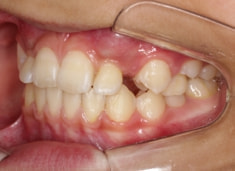

治療前

治療開始時

FX(フェイシャルアキシス)は85度なので東洋人の平均値に近く、下顎が前方に過剰成長するリスクは強くはありません。

しかしやはり上顎は劣成長で、下顎が優位な状態ではあります。

上下顎のギャップはありますが、顔面自体の幅径は良好な値を示していますので、スペース不足は拡大することによって解決できポテンシャルはあると考えられます。

左右の非対称もさほど強くありません。